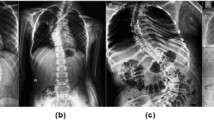

Analyzing spinal curvatures manually is time-consuming and tedious for clinicians, and intra-observer and inter-observer variability can affect manual measurements. In this study, we developed and evaluated the performance of an automated deep learning–based computer-aided diagnosis (CAD) tool for measuring the sagittal alignment of the spine from X-ray images. The CAD system proposed here performs two functions: deep learning–based lateral spine segmentation and automatic analysis of thoracic kyphosis and lumbar lordosis angles. We utilized 322 datasets with data augmentation for learning and fivefold cross-validation. The segmentation model was based on U-Net, which has multiple applications in medical image processing. Here, we utilized parameter equations and trigonometric functions to design spinal angle measurement algorithms. The kyphosis (T4–T12) and lordosis angle (L1–S1, L1–L5) were automatically measured to help diagnose kyphosis and lordosis. The segmentation model had precision, sensitivity, and dice similarity coefficient values of 90.53 ± 4.61%, 89.53 ± 1.8%, and 90.22 ± 0.62%, respectively. The performance of the CAD algorithm was also verified with the Pearson correlation, Bland–Altman, and intra-class correlation coefficient (ICC) analysis. The proposed angle measurement algorithm exhibited high similarity and reliability during verification. Therefore, CAD can help clinicians in reaching a diagnosis by analyzing the sagittal spinal curvatures while reducing observer-based variability and the required time or effort.